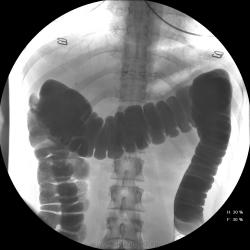

Девушка, 27 лет, жалуется на периодические боли в правой подвздошной области, области паха справа. Во время этого идет нарушение стула - то слабит, то несколько дней не может ходить в туалет, вздутие кишечника. Жалобы несколько лет . Обследованна кем только можно. Хирург посоветовал ирригоскопию. Работа достаточно нервная. До первого случая данных проблем , за неделю, проходила сан лечение в пансионате ( для поднятия общего иммунитета - так говорит), был курс клизм с травами - сама думает, что это не связанно.

Цепочка тенюшек - это наша "гордость)" следы от контраста после гистеросальпингоскопии. чтоб вымыть ,надо разбирать стол , а это только с представителем сименса. вот так.) а правые отделы толстой кишки на расширены? я кроме лополнительной петли сигмы сам ничего не вижу. несколько настораживает некоторое расширение правых отделов кишки- может за счет запоров, которые случаются у девушки? не хочется что то пропустить.

А, чем вызвана неоднородность контрастирования слепой и частично восходящего отдела?

Тугого контрастирования слепой не достигнуто. Должны быть причины.

Слепая кишка в конце исследования, несмотря на её содержимое, заполнилась прилично. А вот гаустрация сигмовидной кишки не сглажена?

Признак долихосигмы - это наличие т.н. симптома "трехстволки", есть это - есть и долихосигма. В данном случае такой вариант имеет место быть.